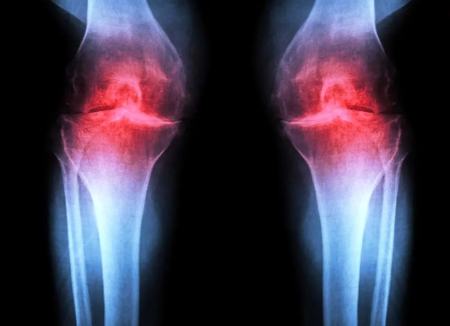

آزمایش موفقیتآمیز داروی جدیدی که میتواند «آرتروز» را درمان کند

به گزارش فرادید، پژوهشگران دانشکدهی پزشکی استنفورد گزارش میدهند که مهار یک پروتئین وابسته به پیری میتواند غضروفی را که بهشکل طبیعی در زانوی موشهای مسن تحلیل میرود، بازسازی کند. در این مطالعه، درمان تزریقی نهتنها غضروف را دوباره ساخت، بلکه پس از آسیبهای زانو نانند پارگی رباط صلیبی قدامی (ACL) که در ورزشکاران و بزرگسالان فعال شایع است، از بروز آرتروز هم جلوگیری کرد. نسخهی خوراکی همین درمان هماکنون در کارآزماییهای بالینی با هدف درمان ضعف عضلانی مرتبط با افزایش سن در حال آزمایش است.

این درمان بهجای تسکین نشانهها، عامل زمینهای آرتروز را هدف میگیرد. این بیماری حادشونده مفصلی حدود یکپنجم بزرگسالان ایالات متحده را درگیر میکند و سالانه حدود ۶۵ میلیارد دلار هزینهی مستقیم مراقبتهای سلامت ایجاد میکند. در حال حاضر هیچ دارویی وجود ندارد که بتواند روند بیماری را متوقف یا معکوس کند و مدیریت درد و تعویض مفصل گزینههای اصلی درمان هستند.

آرتروز زمانی رخ میدهد که مفصل بر اثر پیری، آسیب یا چاقی تحت فشار قرار گیرد. کندروسیتها شروع به آزادسازی مولکولهای پیشالتهابی و تجزیهی کلاژن (پروتئین ساختاری اصلی غضروف) میکنند. با از دست رفتن کلاژن، غضروف نازک و نرم میشود و التهاب همراه، تورم و درد مفصل را (که از ویژگیهای بارز بیماری است) ایجاد میکند. در شرایط عادی، غضروف مفصلی بهندرت بازسازی میشود. اگرچه برخی جمعیتهای فرضی از سلولهای بنیادی یا پیشسازِ قادر به تولید غضروف در استخوان شناسایی شدهاند، تلاشها برای یافتن جمعیتهای مشابه در غضروف مفصلی موفقیتآمیز نبوده است.